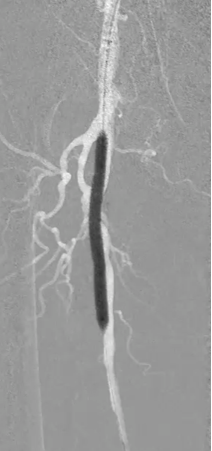

因患者股浅动脉及腘动脉狭窄闭塞段均严重钙化,选择使用振波球囊(6mm*80mm、5mm*80mm)

分别对股浅动脉、腘动脉狭窄闭塞段扩张(球囊至4atm,3级振波强度3个循环,5级振波强度3个循环);球囊切迹逐渐消失

IVUS提示病变段仍有局部重度狭窄,遂选择最新上市的”始祖鸟”紫杉醇药物涂层球囊(5*150mm、6*150mm )对残余狭窄进行扩张

IVUS提示病变段仍有局部重度狭窄,遂选择最新上市的”始祖鸟”紫杉醇药物涂层球囊(6*150mm、 5*150mm ) 分别对股浅动脉、腘动脉、胫腓干动脉逐段扩张,压力至工作压维持3分钟。

步进造影配合血管腔内超声诊断导管提示:股浅动脉全程、腘动脉、胫腓干动脉血流通畅,未见明显夹层、造影剂外溢,远端未见栓塞,膝下动脉如前。